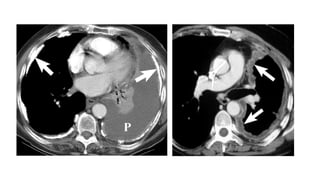

Es necesario la administración de contraste intravenoso para poder valorar el realce de la

pleura y diferenciar el derrame del parénquima pulmonar atelectasiado.

HALLAZGOS TAC

• Engrosamiento nodular pleural o crecimiento tumoral pleural con

morfologia de corteza (Rind-like)

• Derrame pleural unilateral

• Engrosamiento tumoral de las cisuras

• 10-52% Placas pleurales calcificadas

• Pérdida de volumen hemitórax afecto

• Ausencia de reexpasión pulmonar tras toracocentesis evacuadora

Diagnóstico: Es necesario laadministración de contraste intravenoso para poder valorar el realce de la pleura y diferenciar el derrame del parénquima pulmonar atelectasiado. HALLAZGOS TAC • Engrosamiento nodular pleural o crecimiento tumoral pleural con morfologia de corteza (Rind-like) • Derrame pleural unilateral • Engrosamiento tumoral de las cisuras • 10-52% Placas pleurales calcificadas • Pérdida de volumen hemitórax afecto • Ausencia de reexpasión pulmonar tras toracocentesis evacuadora